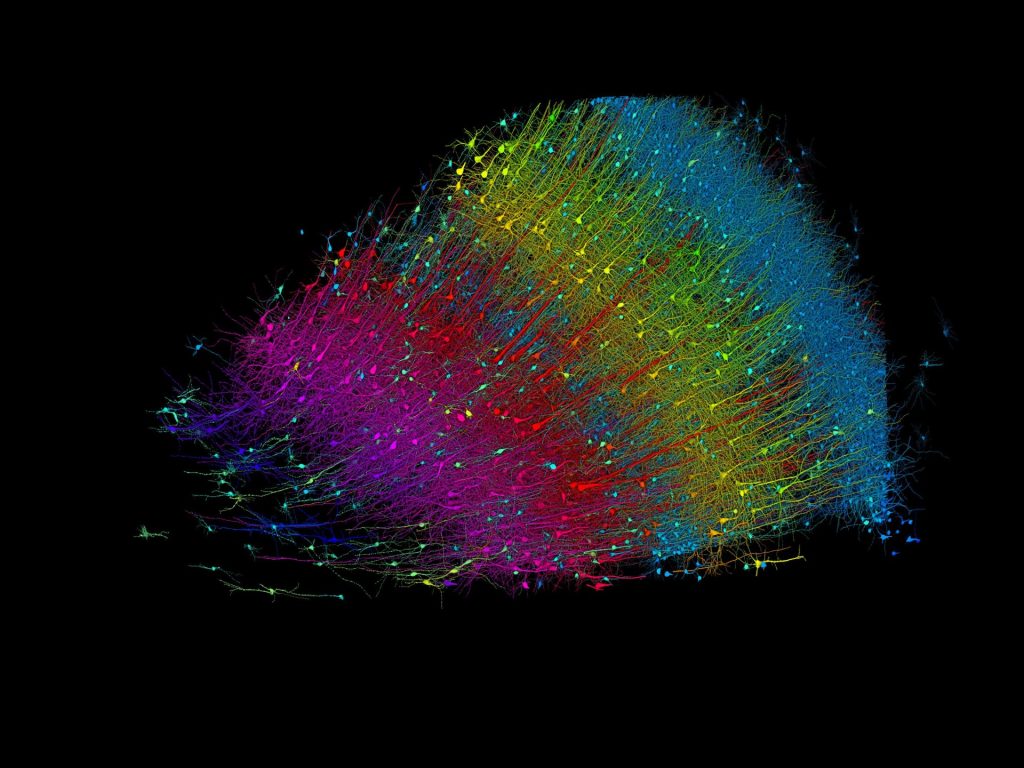

أقدم فريق علمي من جامعة هارفارد بالمشاركة مع باحثين من شركة “غوغل” على إنشاء نموذج ثلاثي الأبعاد لجزء صغير من الدماغ بدقة متناهية. ويوضح النموذج كلّ خلية توجد فيه على حدة، والروابط العصبية التي تجمع بين بعضها البعض، في حين لا يتجاوز النموذج نصف حجم حبة الأرز.

وعلى الرغم من حجمه البالغ الصغر الذي لا يتجاوز نحو مليمتر مكعب واحد، فإنّ النموذج مليء بالتفاصيل الهائلة والدقيقة، إذ يحتوي على 57 ألف خلية، و230 ملم من الأوعية الدموية، و150 مليون مشبك عصبي، والتي تشكل معًا 1400 تيرابايت من البيانات.

واستغرق العمل على هذا الإنجاز الذي نُشِر في مجلة “ساينس” الدورية قرابة 10 سنوات، عن طريق دمج التصوير المجهري الإلكتروني وخوارزميات الذكاء الاصطناعي لتشفير الألوان وإعادة بناء الروابط المعقدة لأدمغة الثدييات.

ويعد الهدف النهائي من المشروع البحثي هو إنشاء خريطة كاملة وعالية الدقة لجميع الروابط العصبية في دماغ الفأر، ومن المقدّر أن يتطلّب الأمر نحو 1000 ضعف كميّة البيانات الحالية التي توصّل إليها العلماء.

ويقول قائد الفريق العلمي الدكتور “جيف ليشتمان”: إنّ توصيف النموذج الذي صُنِع بأنّه “جزء صغير” لا يعكس وجه الحقيقة، فَتَحت هذا الجزء يندرج الكثير والكثير من التفاصيل الدقيقة.

وتحتوي الخريطة الحديثة على تفاصيل لم تُعرض من قبل لبنية الدماغ، بما في ذلك مجموعة نادرة من المحاور العصبية (الألياف العصبية) المتصلة بنحو 50 مشبكا عصبيا. ولاحظ الفريق أيضا وجود بعض الشذوذ في الأنسجة، مثل وجود محاور عصبية شكّلت تجاعيد شديدة الانحناء. وبحكم أنّ الدراسة أجريت على عيّنة لمريض مصاب بالصرع، فلا يدرك الباحثون إذا ما كانت هذه الانحناءات نتاجا لحالة مرضية أم أنها طبيعية.

وأتاحت خوارزميات الذكاء الاصطناعي المتطورة من عملاق التكنولوجيا “غوغل”، إعادة بناء أنسجة الدماغ ورسم خرائط ثلاثية الأبعاد، كما أنّ الفريق طوّر مجموعة من الأدوات وجعلها متاحة لجميع الباحثين لاستخدامها في المستقبل.